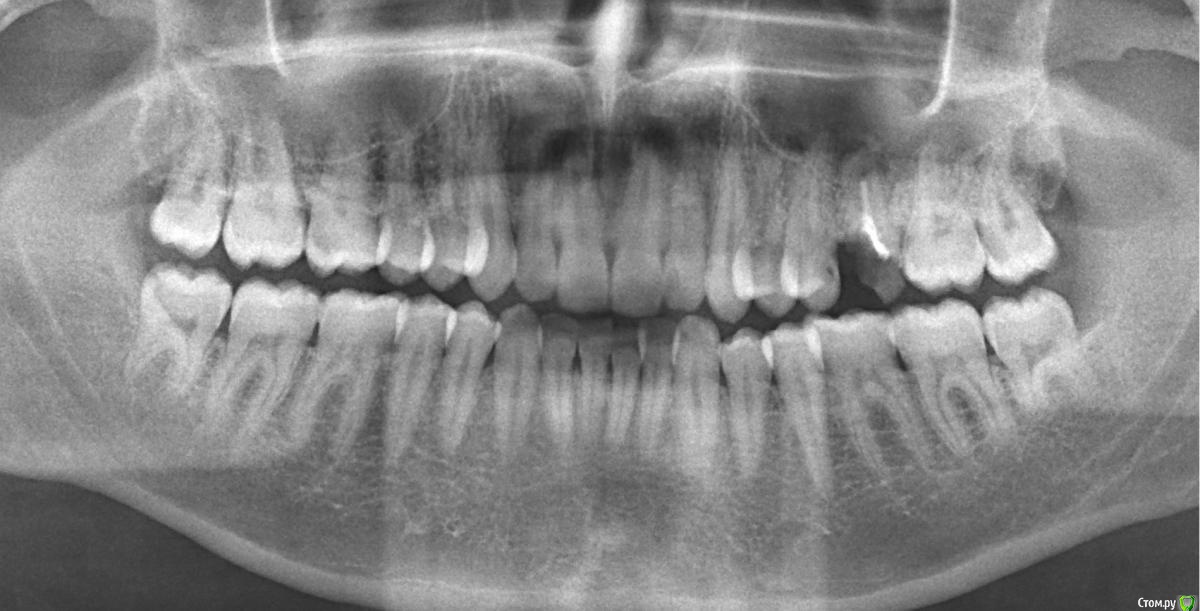

wainerrr Опубликовано 16 апреля, 2016 Поделиться Опубликовано 16 апреля, 2016 Здравствуйте! 3 дня назад выпала пломба, разрушился зуб, корни остались. Болевые ощущения пока не испытываю.Хотелось бы узнать стоит ли удалять сразу либо:1. перелечить корни, запломбировать и оставить (насколько это надежно и долго продержится ? )Как мне объяснили при выдаче снимка - залечен один корень и тот не до конца, остальные не тронуты, вокруг корня есть воспалениеВ августе 2015г. в этом месте был периодонтит вокруг корня, принимал цифран СТ500, прошло2. Есть ли он сейчас периодонтит (судя по снимкам)?3. До лечения нужно решить вопрос с периодонтитом?4. Как лучше перелечить:1) просто запломбировать корни ?2) запломбировать корни и установить в корни анкерные штифты (или стекловолоконные) на которые наростить пломбу ?3) запломбировать корни и установить в корни разборную штифтовую вкладку на которую наростить пломбу ? Каковы риски дальнейших воспалительных процессов при перелечивании ? 5. На зубе, находящимся рядом с разрушенным один врач глядя на потемнение сказал, что надо лечить, дугой сказал,что зуб в порядке -Ваше мнение? Спасибо ! Ссылка на комментарий

Ker Опубликовано 16 апреля, 2016 Поделиться Опубликовано 16 апреля, 2016 (изменено) Корни просто удалить, периодонтит есть и не маленький, соседний зуб лечить 100%. Изменено 16 апреля, 2016 пользователем Ker Ссылка на комментарий